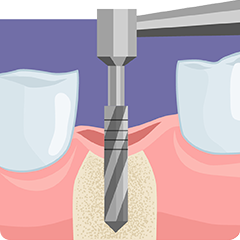

STEP

1

一次手術

歯を失った箇所の歯槽骨にドリルで穴を開けます。

約2~3か月